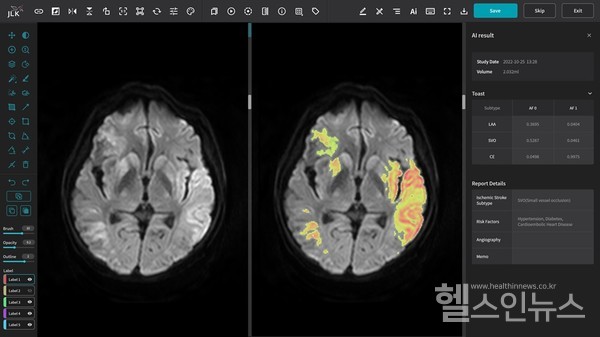

보건복지부는 지난 26일 제21차 건강보험정책심의위원회를 통해 AI 의료기기의 건강보험 비급여를 제이엘케이의 뇌졸중 솔루션 ‘JBS-01K’(뇌경색 유형분류)에 부여했다.

제이엘케이는 “당사는 높은 수준의 기술력을 기반으로 뇌졸중 전 주기를 대응하는 세계 최다 솔루션을 보유하고 있으며, 인공지능 분야 혁신의료기술에 대한 최초 건강보험 적용 사례로 국내 1호로서 입증도 완료됐다”며, “11개 솔루션을 차례로 건강보험 수가를 적용받아 의료 현장에 선보일 예정”이라고 전했다.